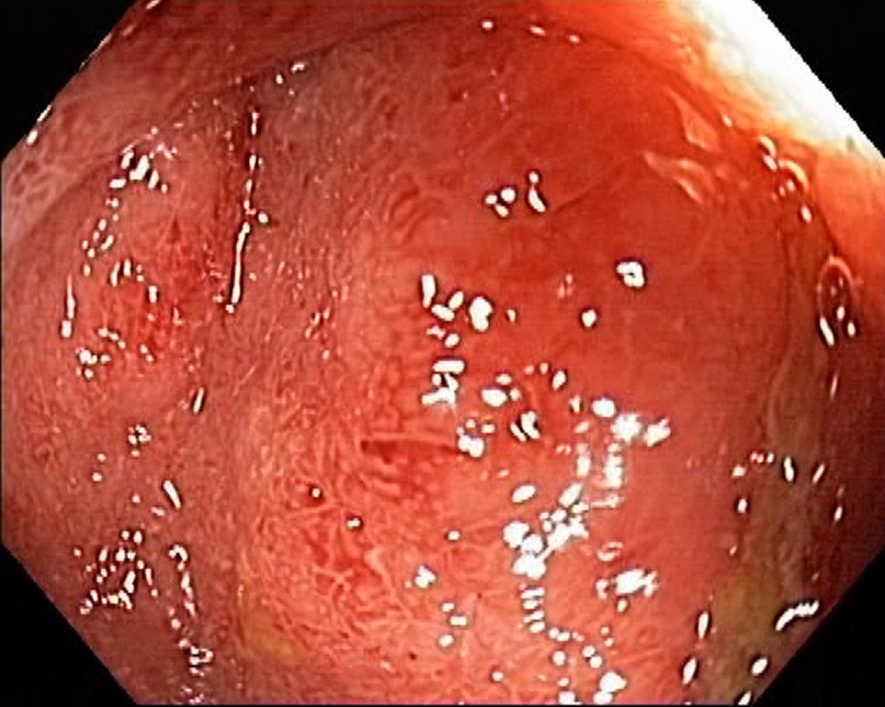

Campylobacter-Colitis